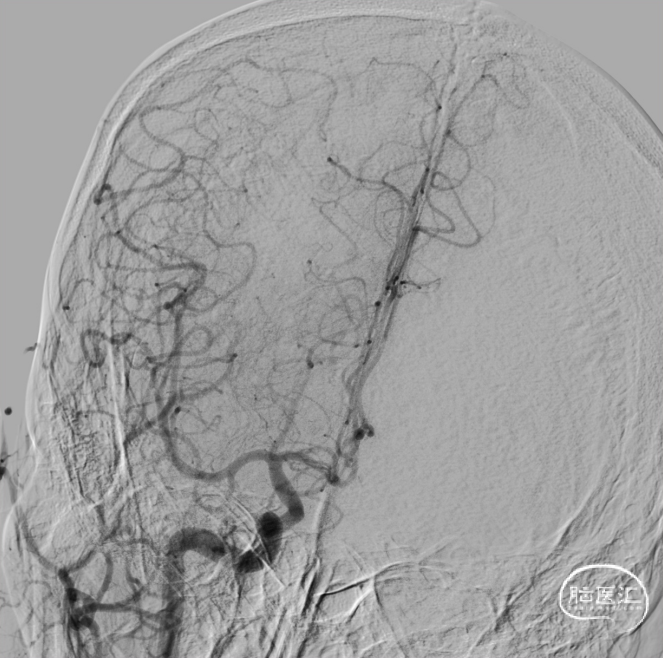

单弯导管、泥鳅导丝引导8F天梯高性能长鞘进入颈内动脉。

置入心玮吞川088颅内血栓抽吸导管到颈升段。

置入6.0*35mm 取栓支架远端保护。

取栓支架到位后,造影示血栓无逃逸。

支架保护下予心玮吞川088颅内血栓抽吸导管行栓子抽吸。

血栓影减少一半。

再来一把SWIM取栓。

血栓影大部分清除。

远端血管灌注改善,mTICI 2c。